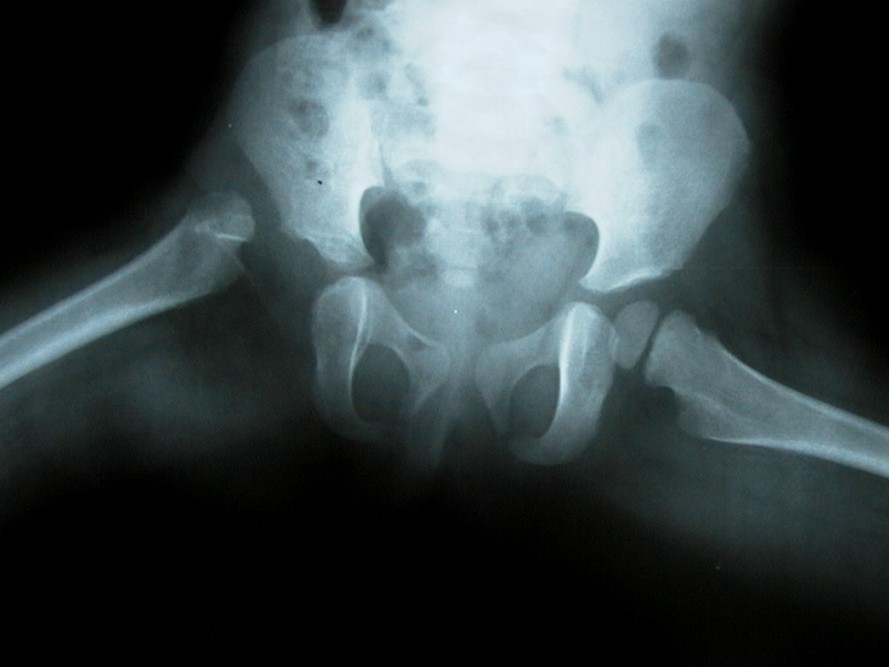

SEcuela de artritis infecciosa

Paciente masculino dos años y medio.

Al año de vida sufre fiebre, aumento de volumen con dolor de la cadera derecha.

Secuela de artritis infecciosa.